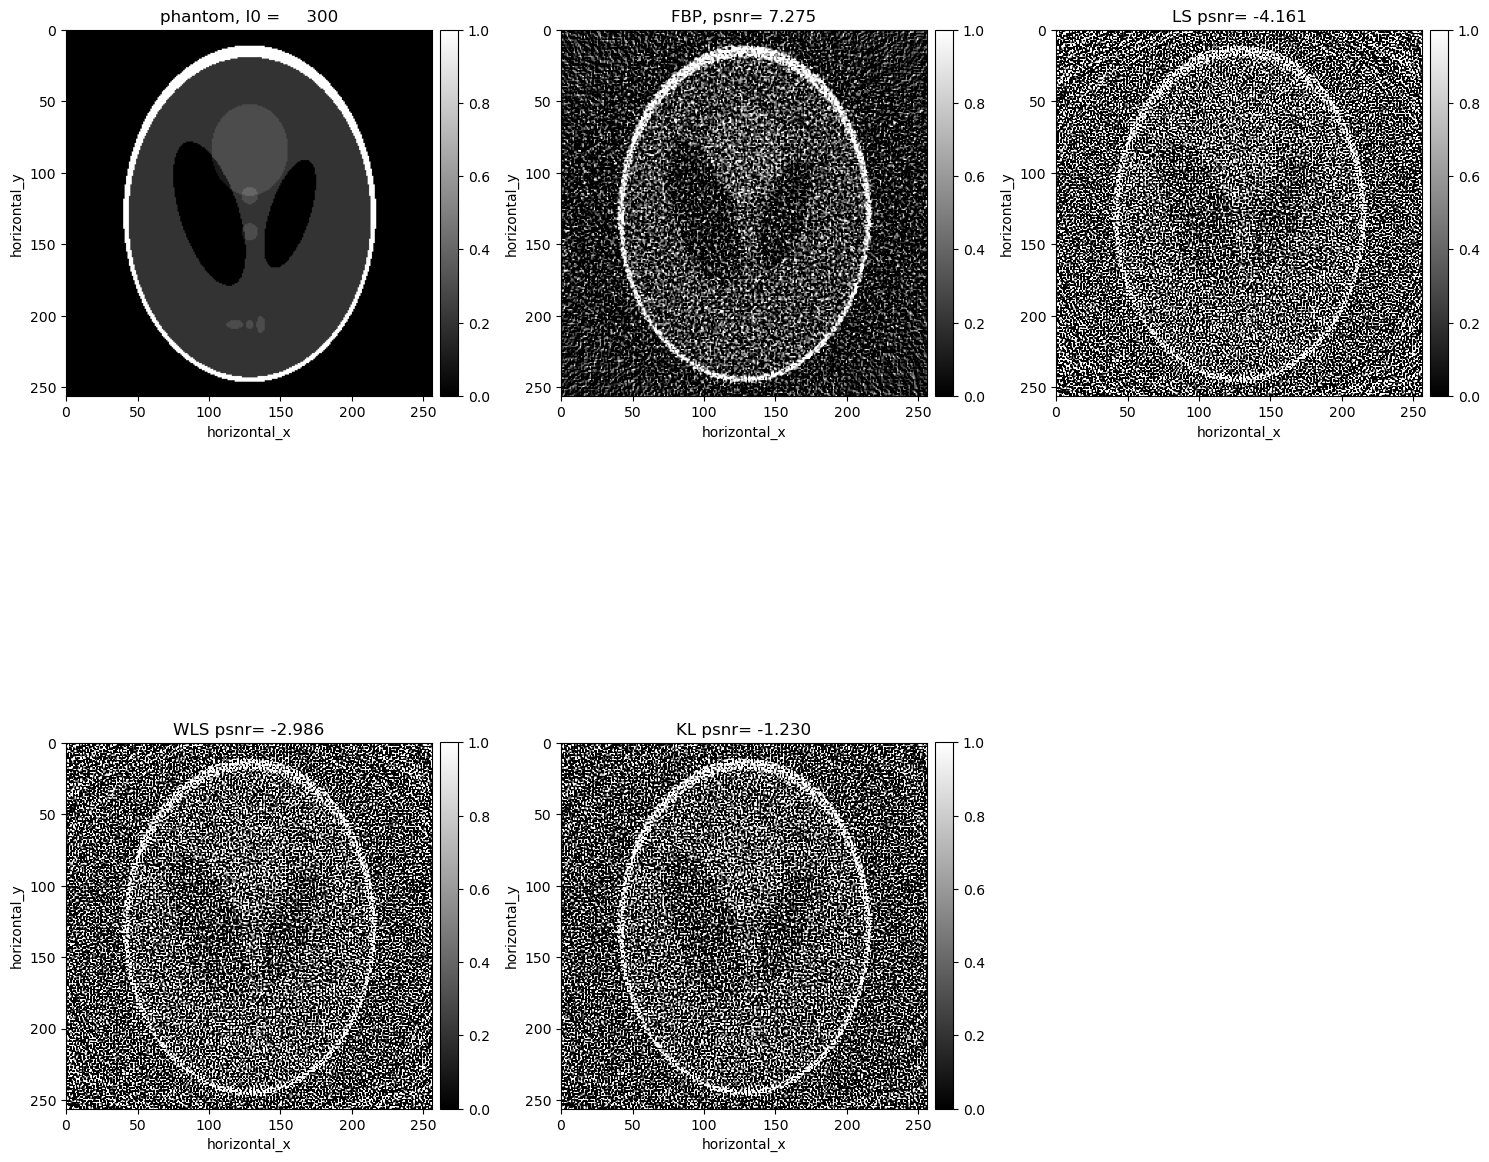

Comparisons without regularisation#

show2D([phantom, recon_fbp, recon_ls,recon_wls, recon_kl ], ["phantom, I0 = %7.0f" % (background_counts), "FBP, psnr= %5.3f" % (psnr_fbp),\ "LS psnr= %5.3f" % (psnr_ls),\ "WLS psnr= %5.3f" % (psnr_wls), \ "KL psnr= %5.3f" % (psnr_kl)], \ cmap=cmap, fix_range =(0,1), num_cols=3, origin='upper-left')

The KL reconstruction is better than the WLS reconstruction which is better than the LS reconstruction. However, all the above reconstructions are worse than the FDK reconcstruction and seem to be overfitting to the noise. In the next section, we consider reconstructions with TV regularisation.